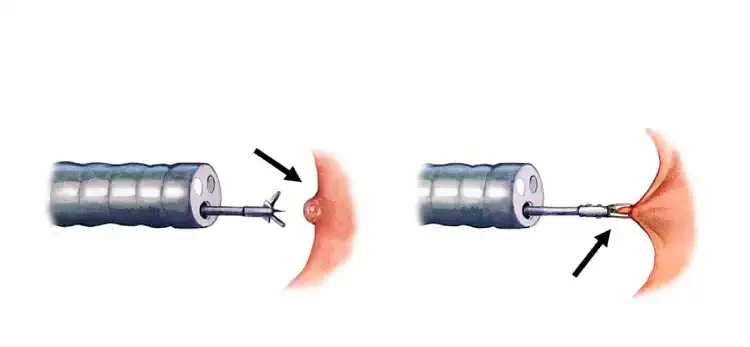

همانطور که در تصویر زیر مشاهده میکنید، پزشک از ابزاری ویژه که در سر لوله کولونوسکوپ تعبیه شده برای برداشتن پولیپهای کوچک استفاده میکند.

برای پولیپهایی با اندازه بیش از ۵ میلیمتر، پولیپکتومی با عبور یک حلقه سیمی از داخل کولونوسکوپ انجام میشود تا پایه پولیپ را احاطه و محکم بگیرد. سپس با کمک الکتروکوتریزاسیون، پولیپ بهطور ایمن برداشته میشود.

در تصویر زیر، میتوانید نحوه گیر انداختن و برداشتن پولیپهای بزرگتر از ۵ میلیمتر را مشاهده کنید.